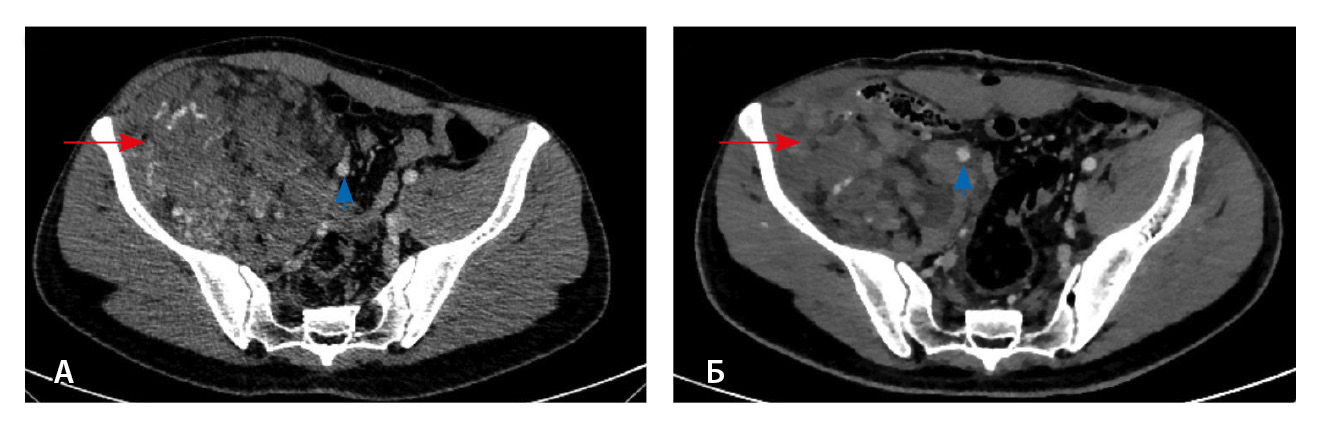

При контрольной томографии, проведенной на 5-е сутки после операции, забрюшинно справа определялась остаточная ткань опухоли размерами 125 × 81 × 90 мм. Резидуальный фрагмент прилегал к правой подвздошной кости, по ходу подвздошных сосудов, с распространением на переднюю поверхность правого бедра. Признаков экстравазации контрастного препарата не обнаружено (рис. 3).

Рис. 3. Мультиспиральная компьютерная томография органов брюшной полости и забрюшинного пространства с болюсным внутривенным контрастированием, венозная фаза. А – исследование до операции, Б – исследование после операции: резидуальный фрагмент образования (красная стрелка) тесно прилежит к подвздошной кости и подвздошным сосудам (головка синей стрелки)